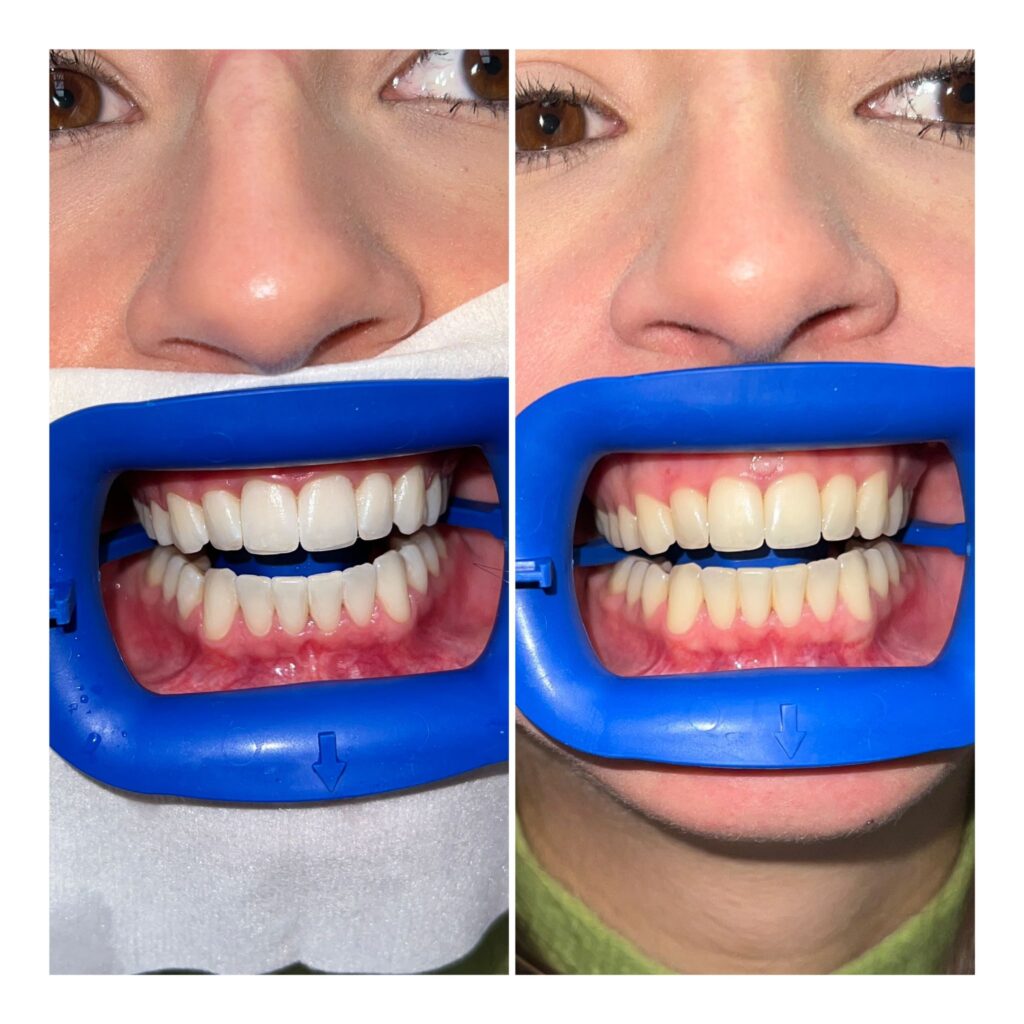

Albire dentară profesională

Albirea dentară profesională este o procedură minim invazivă, menită să redea dinților o nuanță mai deschisă, păstrând sănătatea smalțului. Tratamentul se realizează sub supraveghere medicală, cu materiale testate clinic, adaptate sensibilității fiecărui pacient.

Rezultatul este un zâmbet mai luminos, uniform și natural, fără efecte artificiale sau deteriorarea structurii dentare.

Beneficii

Procedură sigură, realizată în cabinet

Control medical al intensității albirii

Rezultate vizibile și uniforme

Respectarea smalțului dentar